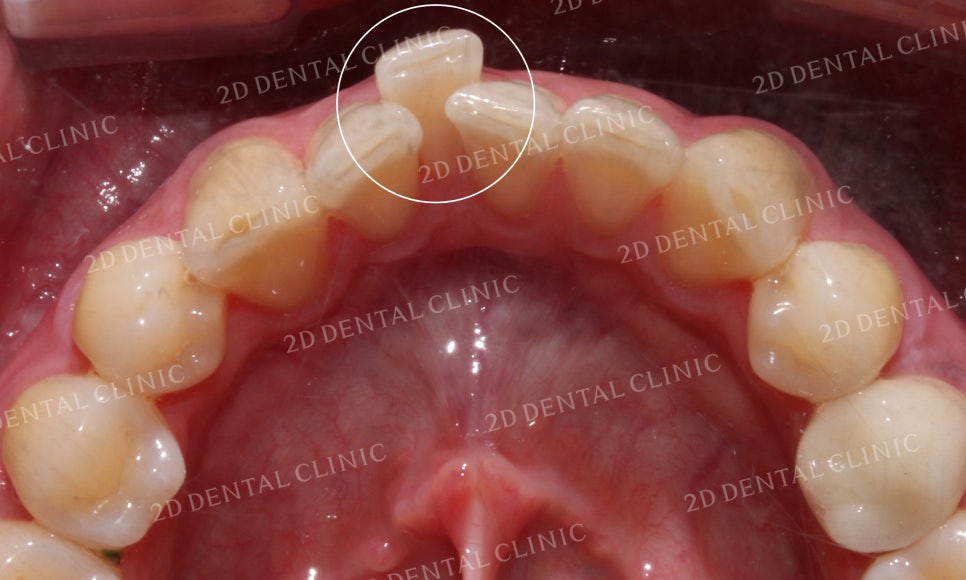

상악 설측면의 사진입니다.

위에서 말했던 것처럼

21번 치아가 회전되어 있어서

측정치가 설측으로 들어와 있는

상황입니다.

표시된 부분의 21번 치아가

유독 회전이 심한 모습이었는데요

이로 인해 측절치가 중절치의

뒤쪽으로 파고들면서

치간에 치석과 플라그가 쌓이고 있는 상태였습니다.

그러나 교정 후 치아가 겹쳐진 부분들이 사라지고

삐뚤거리던 크라우딩도 사라지면서

가지런해진 치아들을 볼 수 있습니다.